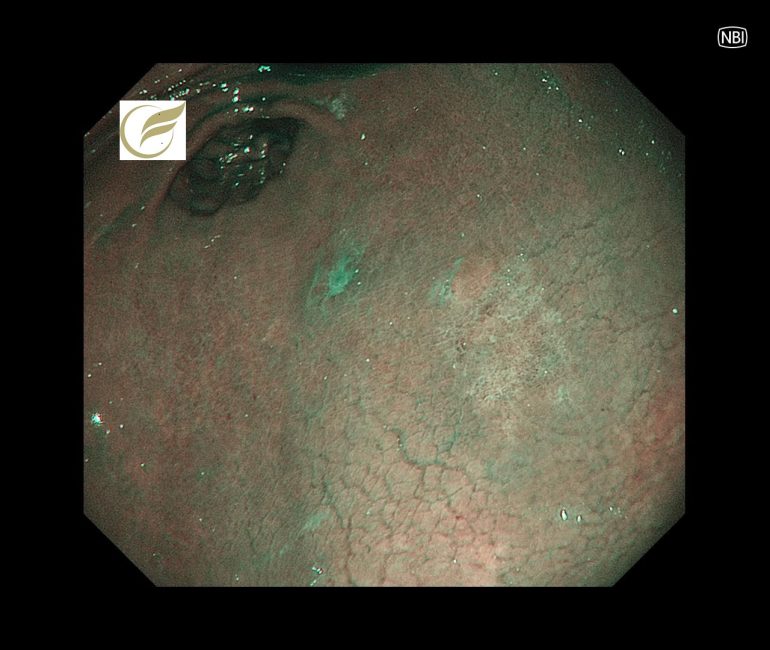

初期像は、内視鏡でわずかな退色調の平坦・陥凹病変として認められることが多く、早期診断には内視鏡観察が必要です(4)。

以下は当院で経験されたピロリ陰性の印環細胞癌(早期癌)の症例です。内視鏡治療で治癒が得られています。